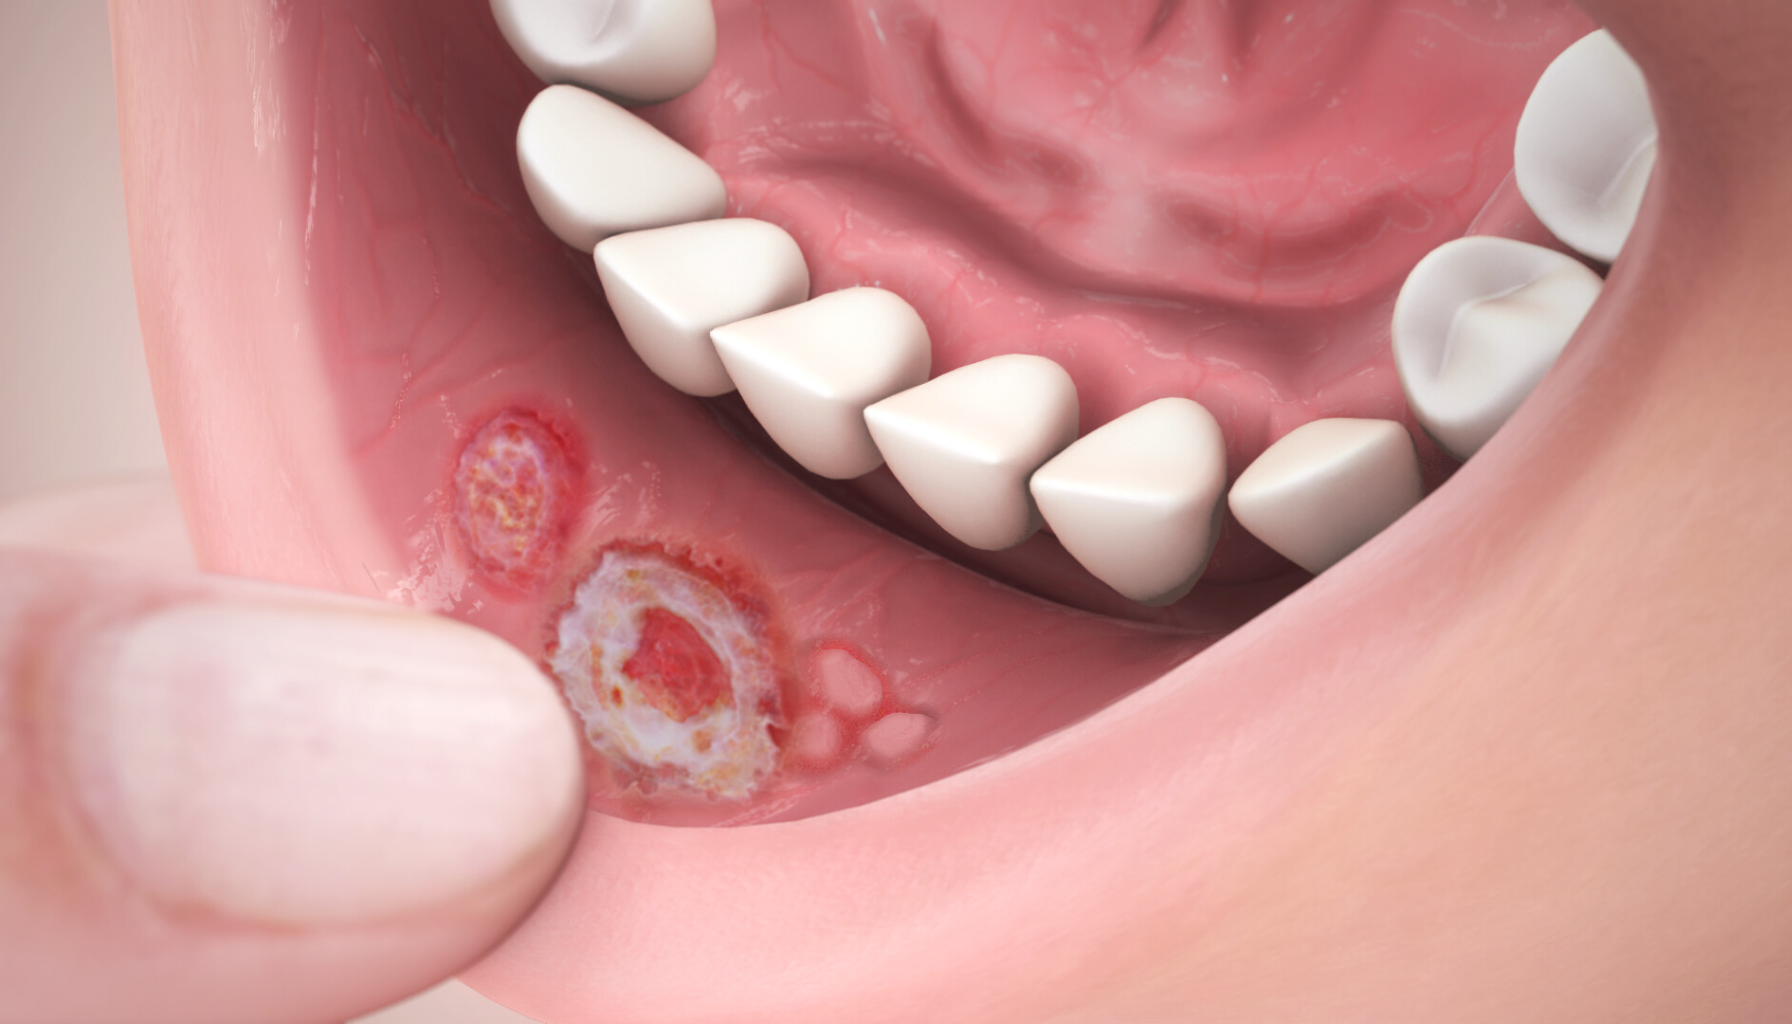

Aftøs stomatitt, ofte kalt after, er en vanlig tilstand som gir små, runde eller ovale sår på slimhinnene i munnen. Sårene er vanligvis hvite eller gulaktige i midten med en rød kant rundt. Tilstanden er ikke smittsom, men kan være svært smertefull og påvirke livskvaliteten.

After oppstår ofte på innsiden av kinn, lepper eller tungen, og varer som regel 1–2 uker. Mange pasienter opplever at tilstanden kommer tilbake regelmessig, og den kan være knyttet til stress, kosthold eller svekket immunforsvar.

- Hva er det: En betennelsestilstand i munnslimhinnen som gir små, runde og smertefulle sår kalt after.

- Symptomer: Røde, runde sår med hvitt eller gult belegg i midten. Gir smerter ved mat og drikke.

Aftøs stomatitt gir smertefulle munnsår som ofte oppstår på innsiden av kinn, lepper eller på tungen. Selv om årsaken ofte er ukjent, kan mangel på vitamin B12, jern eller folsyre, samt stress og irritasjon i munnhulen, bidra til utviklingen.